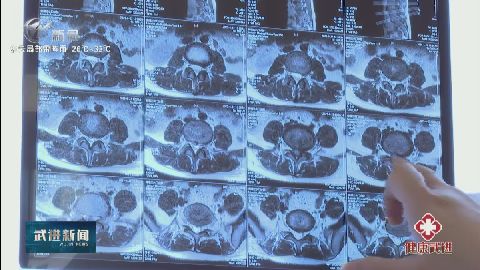

(健康武進(jìn)) 腰椎間盤突出癥“年輕化